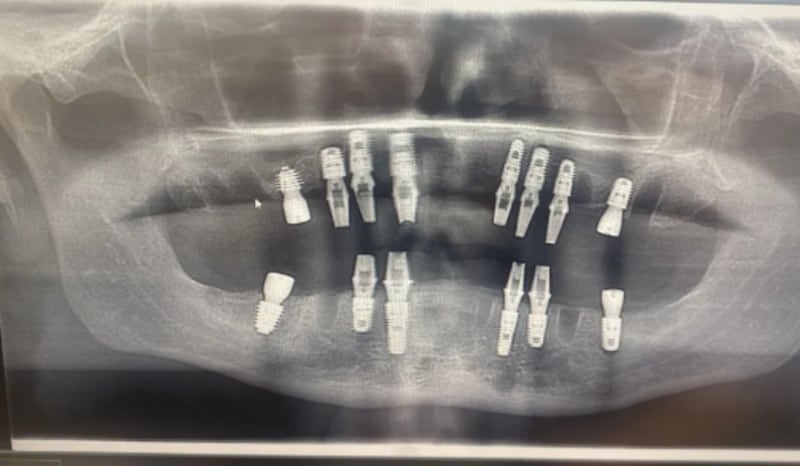

Denton optó por un tratamiento en Turquía por un costo aproximado de USD 4,731.49, donde le colocaron 14 implantes dentales en una sola intervención.

Ante las complicaciones, el hombre regresó a Turquía para una revisión. Sin embargo, asegura que durante el procedimiento, y mientras se encontraba sedado, el dentista decidió retirarle todos los implantes.